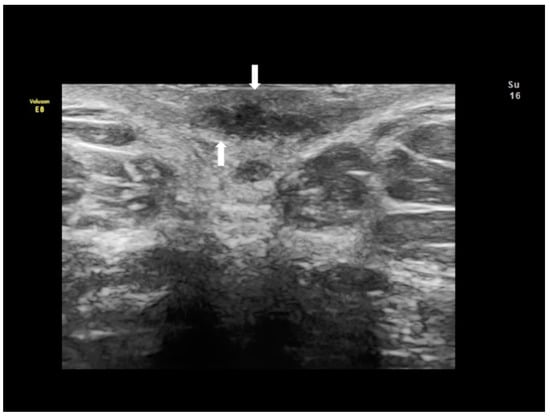

Figure 1. Ultrasonographic images of two nodules (AC) (see white arrows), of scar endometriosis with some color spots (C) due to internal vascularization, infiltrating the external oblique muscle in a woman with a previous cesarean section some years before. Drawing of the location (D).

Scar endometriosis may present as a hypoechoic solid nodule with hyperechoic spots or strands which represent fibrosis within the scar tissue, a hyperechoic peripheral ring, spiculated borders and a single vessel entering the nodule from the periphery (Figure 1 and Figure 2) [11,12,13]. In nodules larger than 30 mm, cystic portions and/or fistulous tract, loss of oval or round shape, multiple vascular pedicles, and central vascularization are more frequent [12].